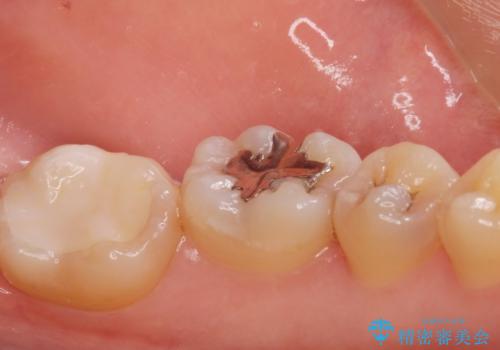

メタルインレーをセラミックインレーに。

- メタルインレーをセラミックインレーに変えたいとの事で来院。

メタルインレーを外し、拡大鏡下でう蝕がないことを確認して

セラミックインレー(e-maxインレー)にて治療しました。